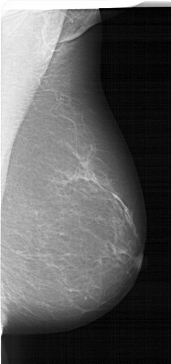

A_1541_1.RIGHT_MLO

RIGHT_MLO LINES 6541 PIXELS_PER_LINE 3076 BITS_PER_PIXEL 12 RESOLUTION 43.5 NON_OVERLAY